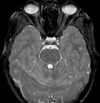

4

Q

A

falx cerebri